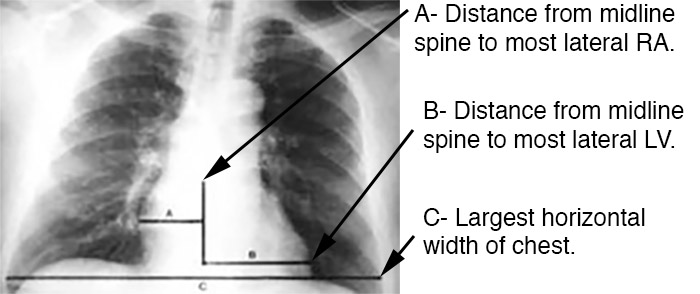

Cardiomegaly is often detected on an anterior-posterior chest x-ray (AP CXR). The standard method for measuring heart size on AP CXR is known as the Danzer Method, and it involves measuring the distance from the midline of the spine to the most lateral aspect of the cardiac apex (distance B, in the image below), and adding this distance to that found from the same midline to the most lateral aspect of the right atrium (distance A). This number is then divided by the largest horizontal width of the chest (distance C), from right to left pleural surface (usually found just above the left hemidiaphragmatic surface). This value (A+B/C) is known as the cardiothoracic ratio (CTR). A CTR > 0.5 indicates cardiomegaly.

Image obtained from the Creative Commons database.